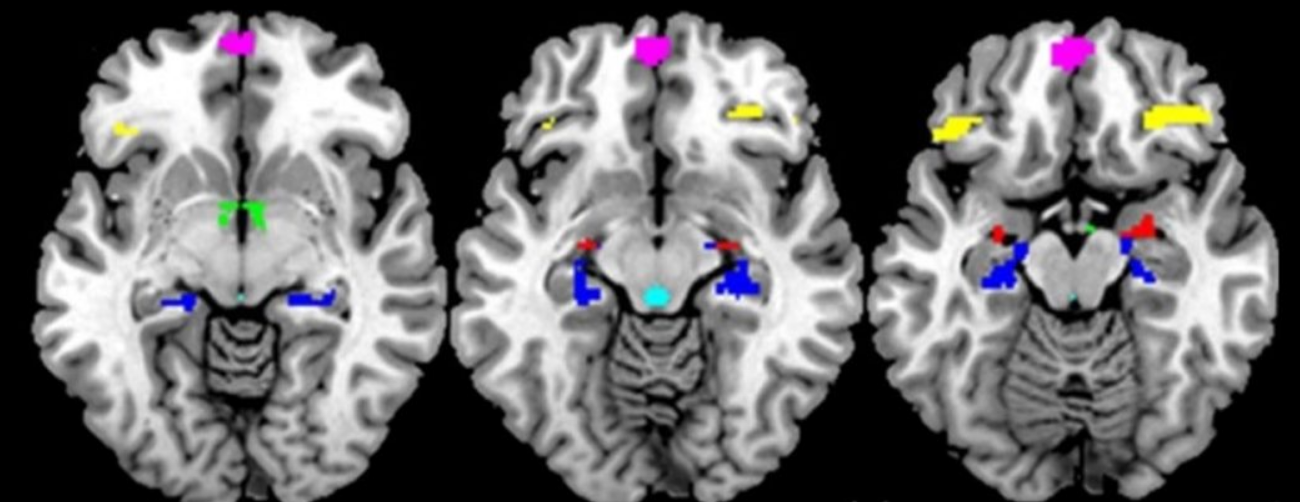

Functional magnetic resonance imaging (fMRI)— that measures brain activity through differences in blood flow within and between different areas of the brain—conducted during a mildly stressful visual challenge showed that exposure to proinflammatory cytokines in the womb significantly affects activity in multiple brain regions and their crosstalk during response to the stressful stimuli in the adult offspring, now around 45 years old.

Arousal in brain regions such as the hypothalamus, amygdala, medial prefrontal cortex, the anterior cingulate cortex and the hippocampus are linked to the stress response of the brain and steroid hormones through the hypothalamic-pituitary-adrenal (HPA) and gonadal axes.

“We study how these brain regions (subcortical arousal regions such as the hypothalamus, brainstem regions and amygdala) are connected to inhibitory control regions (like the anterior cingulate cortex, orbitofrontal region, and hippocampus) and how these connections go awry in disorders like depression, bipolar disorder and schizophrenia. We investigate this not only from a brain activity-connectivity point of view but also associated physiology such as hormonal response, autonomic nervous responses, and immune response,” says Goldstein.

Among other functions, the hypothalamus coordinates brain activity that regulates the release of stress hormones, like cortisol. The study shows lower maternal TNF-α levels are linked to higher hypothalamic activity in both sexes and higher functional connectivity between hypothalamus and anterior cingulate in men but not in women.

The paraventricular nucleus, a sub-region of the hypothalamus, has a high density of TNF-α receptors. “So, it was quite interesting to us that the region significantly affected by adverse maternal TNF-α levels was the hypothalamus in the offspring. There are substantial sex differences in the development of hypothalamic nuclei during gestation and thus this region is vulnerable to differential effects of in utero exposures depending on timing of exposure. Hypothalamic activity under negative stress is expected as the PVN is the key relay station for the regulation of the stress response. The anterior cingulate cortex is one of the regions in the brain that provides inhibitory control of activity in the hypothalamus. So, connectivity between these two regions is important for the regulation of arousal. When it goes awry it can lead to hyperarousal states,” says Goldstein. This is accompanied by overexpression of stress hormones such as cortisol.

The hippocampus, a brain region also endowed with a high density of TNF-α receptors, is important for inhibitory control of arousal as well as functions such as learning and memory. The authors show higher prenatal levels of IL-6 are associated with enhanced hippocampal activity in women but not in men.

When examined in relation to the inflammatory reducing effects of IL-10, the ratio TNF-α to IL-10 is associated with sex-dependent effects on hippocampal activity and functional connectivity with the hypothalamus.